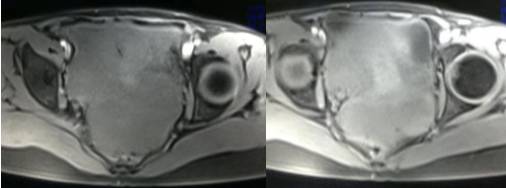

女性,42岁。

主诉:下腹部胀痛不适1月余

病史:自诉13岁时患“结核”,8年前行“左侧附件包块”切除术。

MR检查:

病理结果:黄体血肿

黄体血肿为正常排卵过程中,卵泡层破裂,引起出血,较多的血液潴留在卵泡或黄体腔内形成血肿。

正常黄体直径为15mm左右,以后转变为白体,并在下一个周期的卵泡期自然消退。若黄体内出血量较多,则形成黄体血肿,或称黄体内出血,出血性黄体。黄体血肿多为单侧,一般直径为40mm,偶可达100mm,黄体血肿被吸收后可导致黄体囊肿,较大的血肿破裂时可出现腹腔内出血,剧烈腹痛、少量阴道流血和腹膜刺激征,不易与宫外孕区别。

根据时间不同MR信号也有所不同,TIWI脂肪抑制序列可以鉴别脂肪和出血。